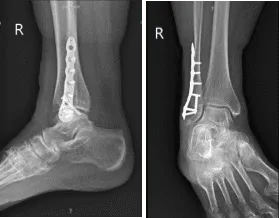

An interfragmentary screw was planned and a 3.5-mm interfragmentary screw was inserted after drilling across the fracture site. Distal fibular plate was put and held by olive wires and checked under fluoro and found to be in acceptable position.

X-ray Right ankle minimum 3 views

The fracture was well reduced. The distal fibular plate was fixed to the fibula with the use of a combination of locking and nonlocking screws. Final picture was taken under rotational fluoroscopy and found to be in an acceptable position. The wound was irrigated and drained.

The patient was seen for post operative check up after three weeks with X-ray results that showed healing distal fibula fracture status post ORIF, without evidence of hardware complications. Comparison to prior posttraumatic/postoperative radiographs recommended.